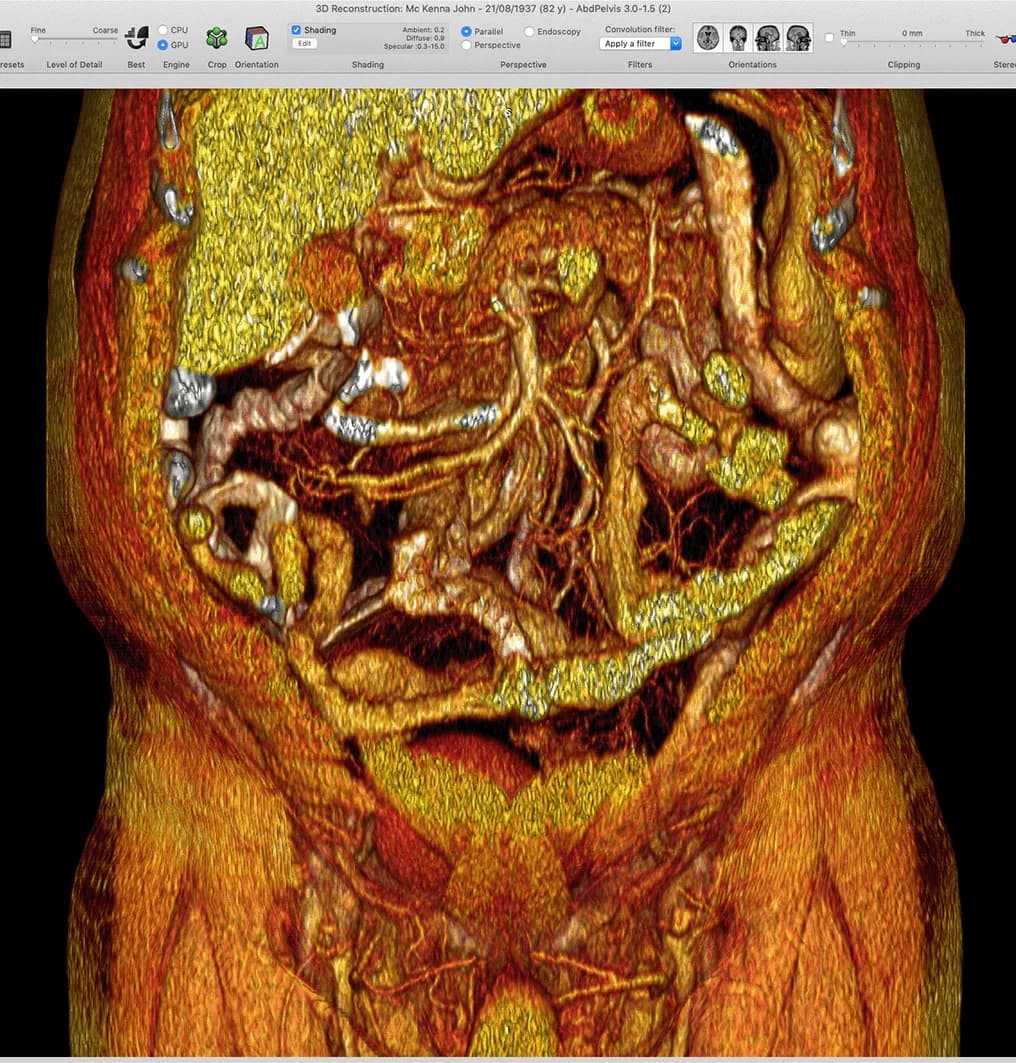

The next major research phase incorporated medical imaging, particularly CT scans, to correlate anatomical findings with radiological appearances. This allowed anatomical continuity and structural relationships to be identified non invasively across large patient populations.

Imaging analysis strengthened the translational value of the research, making findings applicable beyond the operating theatre and dissection room. It also facilitated comparison between normal anatomy and pathological change, reinforcing the clinical relevance of the work.

A defining strength of this project is its longevity. Over more than 14 years, data has been accumulated from multiple sources, disciplines, and technologies. Maintaining consistency across evolving research tools required structured digital organisation, careful versioning, and repeatable analysis processes.

The ability to integrate embryology, cadaveric study, surgical footage, imaging, and disease research into a single coherent body of work demonstrates advanced research coordination and long term data stewardship.